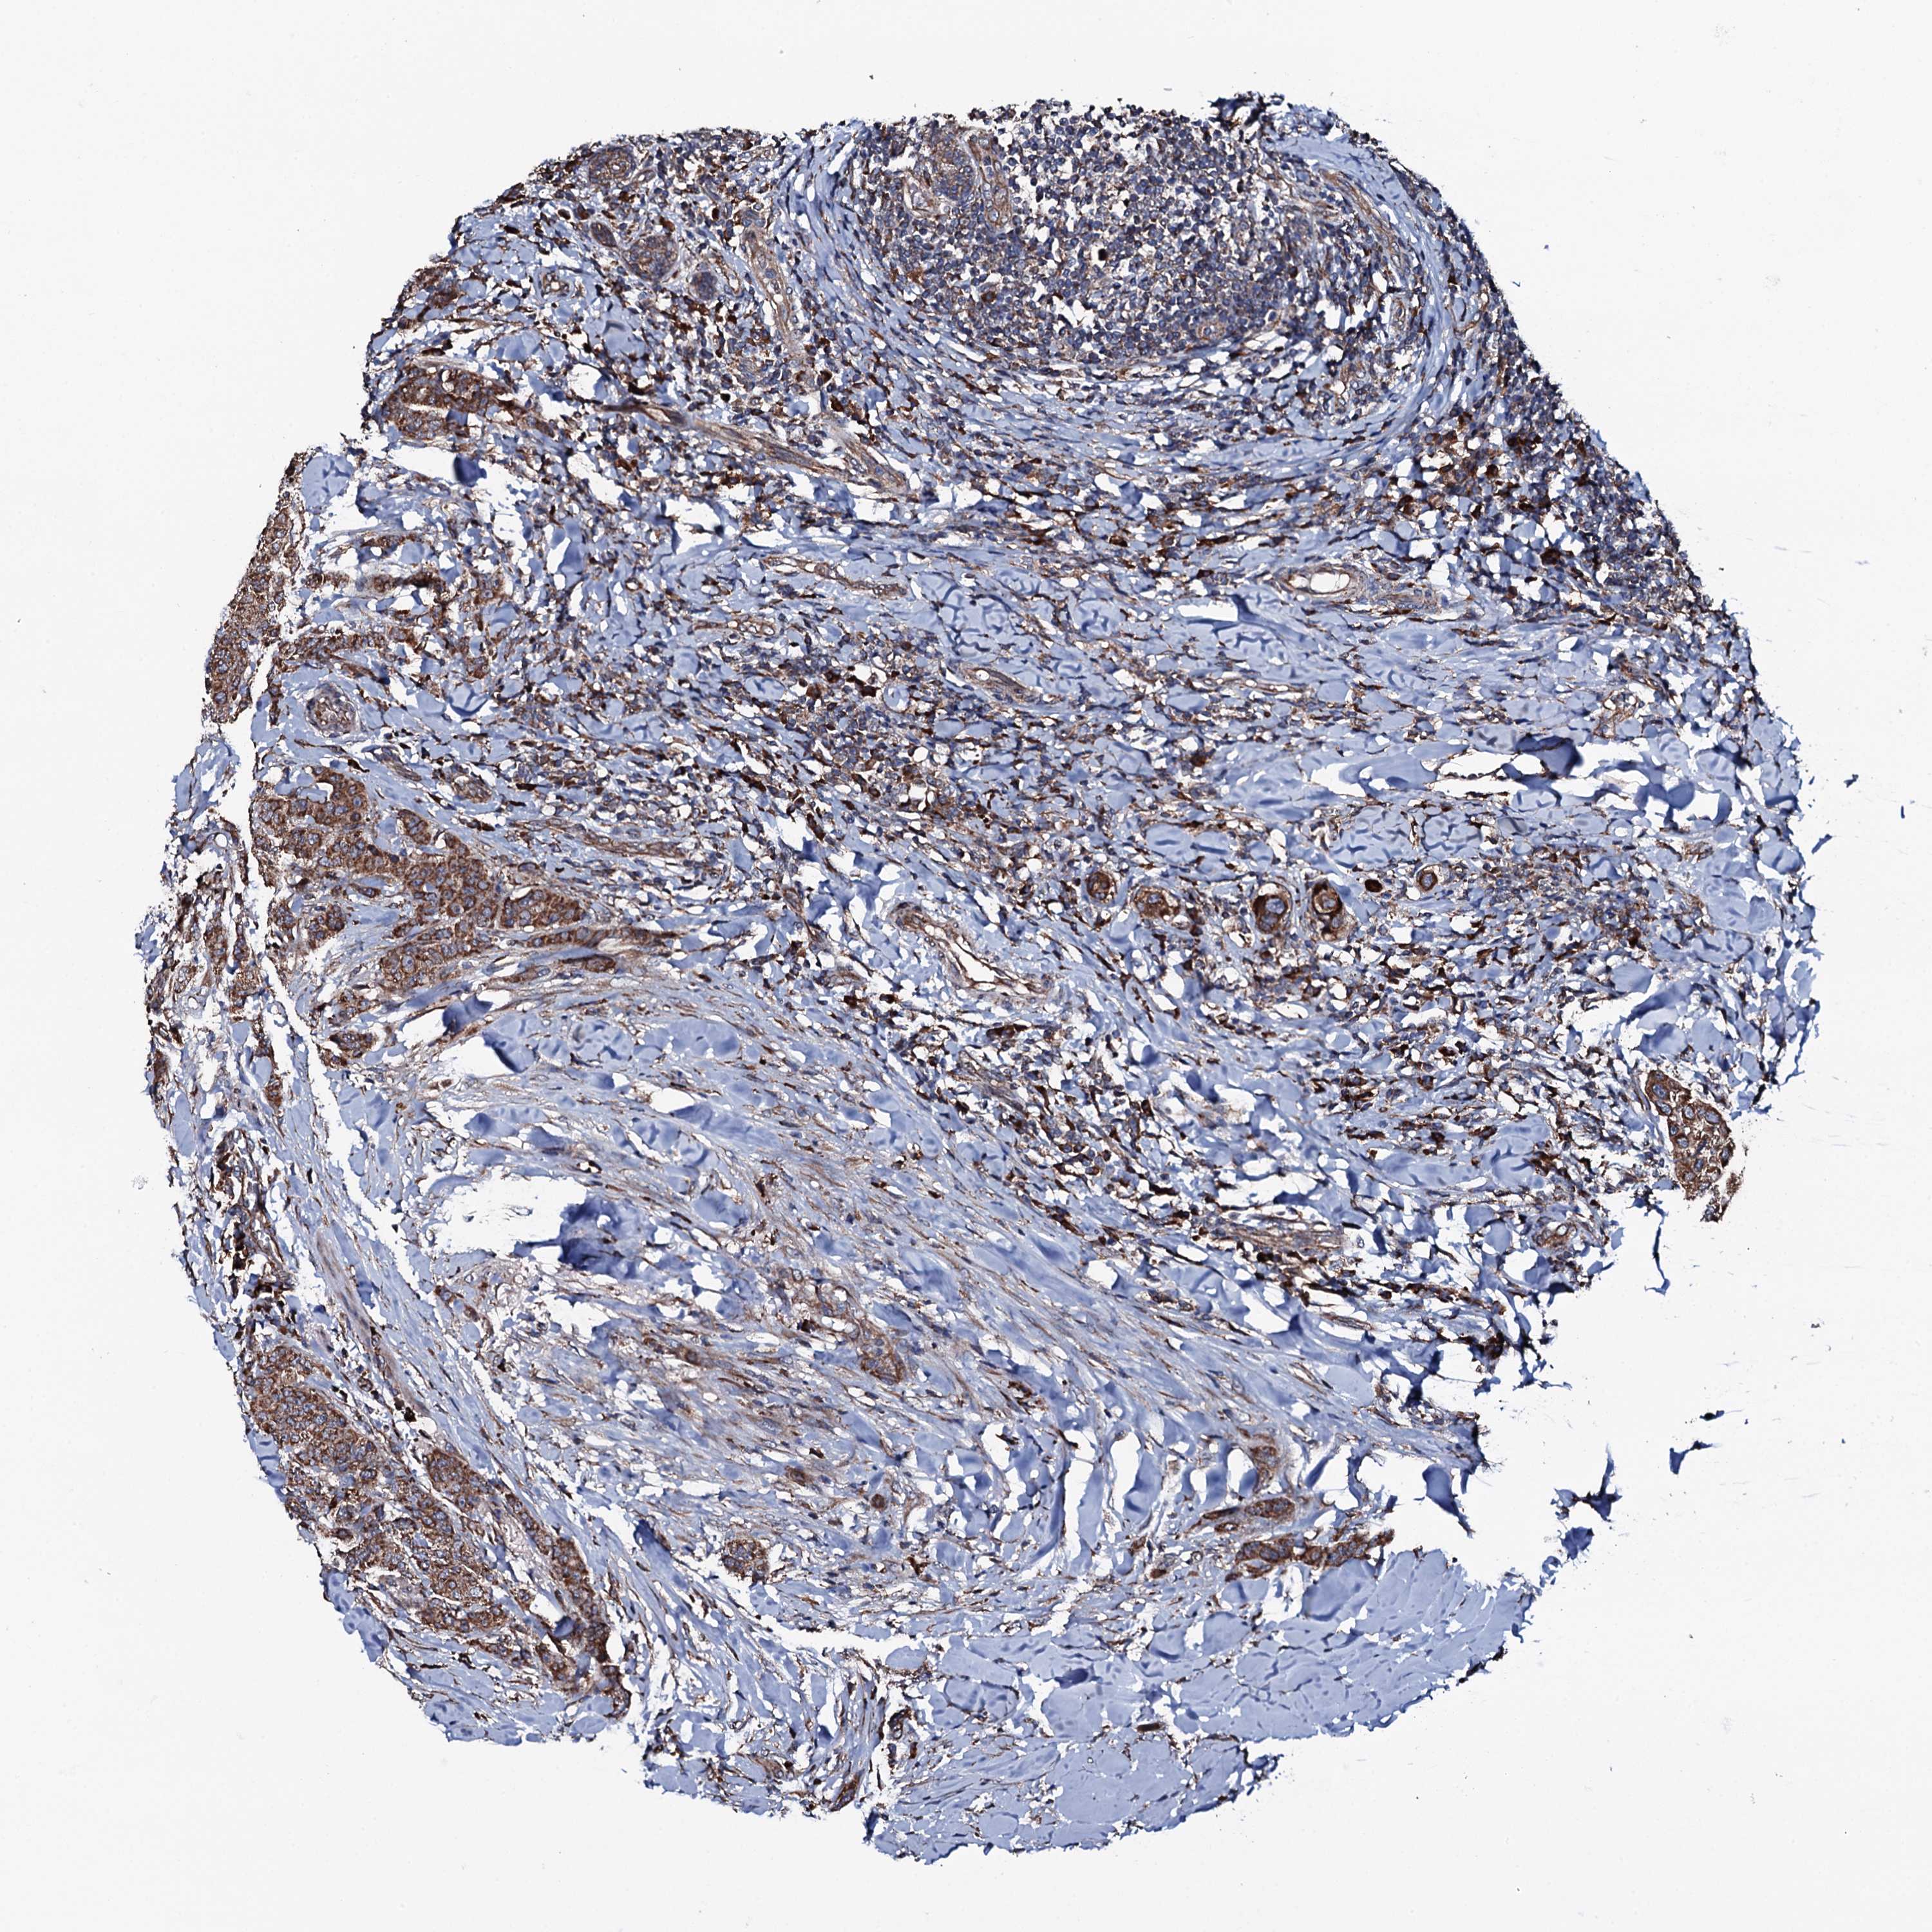

BRCA TCGA BRCA VALIDATION PROTEIN EXPRESSION